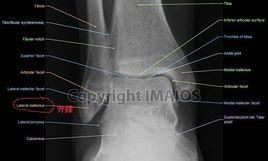

外踝(Malleolus lateralis),解剖結構名。出《靈樞·骨度》。又名核骨。指腓骨下端向外的骨突。

外踝尖作為經外奇穴具有治療拘急,齒痛等急症的作用。

外踝高,從外踝點(mf)至地面的垂距。

英文 釋義外踝尖穴,人體穴位之一,位於足外踝最高點。